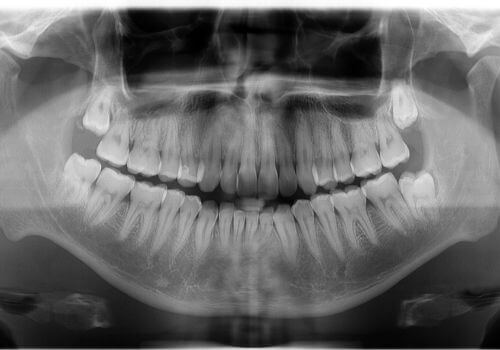

Imagine taking a 360-degree photo of your mouth — that’s essentially what a panoramic X-ray does. This type of X-ray captures your entire mouth, including all your teeth, both upper and lower jaws, and the surrounding structures, in a single image.

When having a panoramic X-ray done, you’ll stand still while a machine rotates around your head. It might sound high-tech (and it is!), but it’s quick, easy, and completely painless. These X-rays are incredibly useful for planning treatments like dentures, braces, or implants. They also help us spot impacted wisdom teeth, jaw disorders, and even some types of tumors.